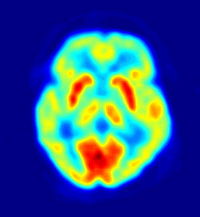

Positron emission tomography (PET) is a nuclear medicine imaging technique that produces a three-dimensional image or map of functional processes in the body. The system detects pairs of gamma rays emitted indirectly by a positron-emitting radionuclide (tracer), which is introduced into the body on a biologically active molecule. Images of tracer concentration in 3-dimensional space within the body are then reconstructed by computer analysis. In modern scanners, this reconstruction is often accomplished with the aid of a CT X-ray scan performed on the patient during the same session, in the same machine.

If the biologically active molecule chosen for PET is FDG ([18F]-fluorodeoxyglucose), an analog of glucose, the concentrations of tracer imaged then give tissue metabolic activity, in terms of regional glucose uptake. This tracer is used in the most common type of PET scan, but other tracer molecules are also used in PET to image the tissue concentration of many other types of molecules of interest.

- Neurology: PET neuroimaging is based on an assumption that areas of high radioactivity are associated with brain activity. What is actually measured indirectly is the flow of blood to different parts of the brain, which is generally believed to be correlated, and has been measured using the tracer oxygen-15. However, because of its 2-minute half-life O-15 must be piped directly from a medical cyclotron for such uses, and this is difficult. In practice, since the brain is normally a rapid user of glucose, and since brain pathologies such as Alzheimer's disease greatly decrease brain metabolism of both glucose and oxygen in tandem, standard FDG-PET of the brain, which measures regional glucose use, may also be successfully used to differentiate Alzheimer's disease from other dementing processes, and also to make early diagnosis of Alzheimer's disease. The advantage of FDG-PET for these uses is its much wider availability. PET imaging with FDG can also be used for localization of seizure focus: A seizure focus will appear as hypometabolic during an interictal scan. Several radiotracers (that is, radioligands) have been developed for PET that are ligands for specific neuroreceptor subtypes such as [11C] raclopride and [18F] fallypride for dopamine D2/D3 receptors, [11C]McN 5652 and [11C]DASB for serotonin transporters, or enzyme substrates (for example, 6-FDOPA for the AADC enzyme). These agents permit the visualization of neuroreceptor pools in the context of a plurality of neuropsychiatric and neurologic illnesses. A novel probe developed at the University of Pittsburgh termed PIB (Pittsburgh Compound-B) permits the visualization of amyloid plaques in the brains of Alzheimer's patients. This technology could assist clinicians in making a positive clinical diagnosis of AD pre-mortem and aid in the development of novel anti-amyloid therapies.